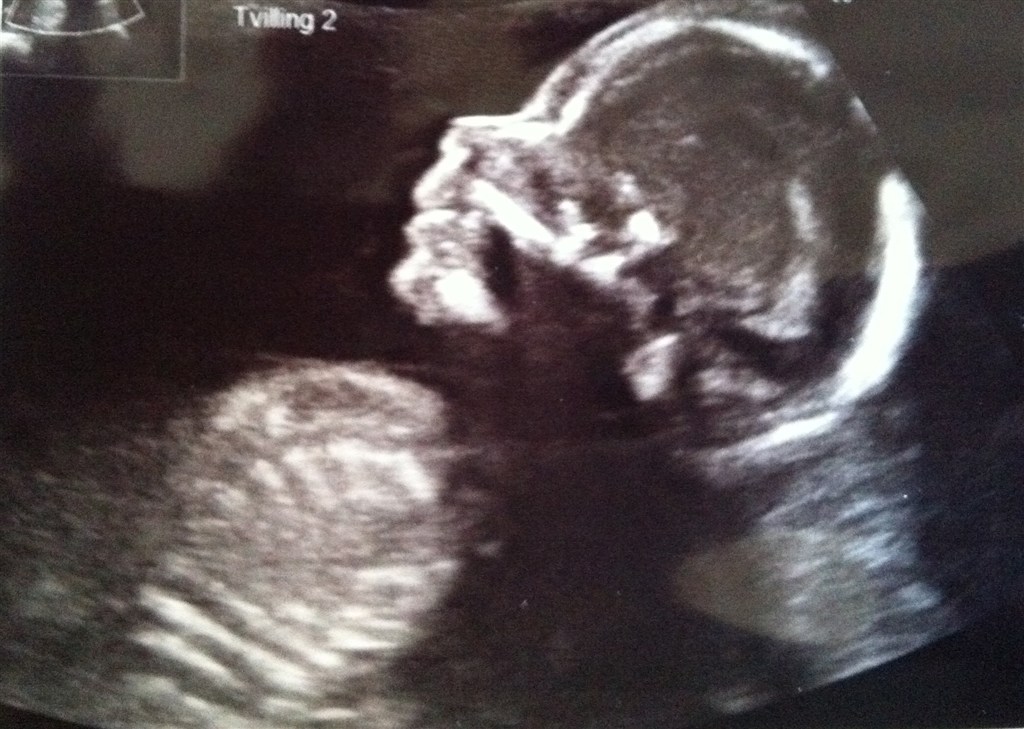

dejligt!! og flotte mavebilleder forresten, der sker lidt når der er to om pladsen

Ha ha, tusind tak. For 14 dage siden kunne man næsten ikke se, at jeg var gravid, men lige pludselig voksede maven helt vildt fra dag til dag. Jeg har taget 10 kg på, men jeg trøster mig selv med at det er normalt, når der er 2